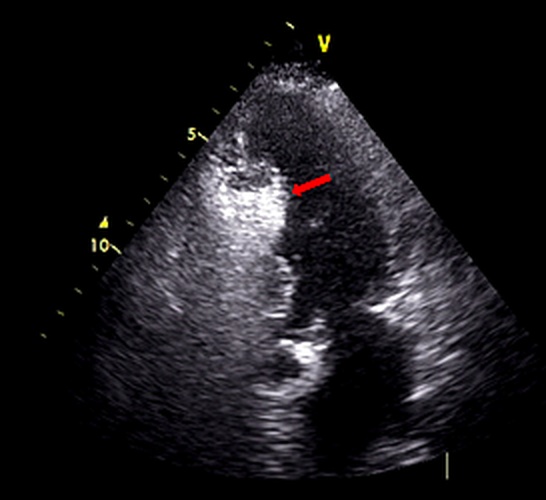

To ensure accurate patient selection, MVOHCM diagnosis was confirmed based on 3 key criteria: (1) a maximum left ventricular (LV) wall thickness of greater than or equal to 15 mm in the absence of any other identifiable cause of hypertrophy, (2) a midventricular pressure gradient of greater than or equal to 30 mm Hg, and (3) a midventricular hourglass-like obliteration due to systolic muscular apposition of the hypertrophic septum against the LV free wall. In some cases, Doppler echocardiography demonstrated a characteristic "signal void" pattern, indicative of abrupt flow cessation across the obliterated ventricle, followed by paradoxical early diastolic flow reflecting the release of previously trapped volume.12 A comprehensive echocardiographic evaluation (Figure 1) was performed to confirm the presence of MVO, characterized by significant myocardial thickening and elevated pressure gradients. This assessment was crucial in identifying candidates suitable for the ablation procedure and optimizing the treatment strategy. Patients were excluded if they had subaortic obstructive HCM, apical HCM, other cardiovascular conditions requiring urgent surgical intervention, or anatomical constraints precluding percutaneous septal reduction therapy.

Comprehensive baseline and follow-up data, including demographic, clinical, and echocardiographic measurements, were collected retrospectively from the hospital’s electronic records, allowing for a detailed analysis of patient profiles and procedural outcomes within a defined cohort. Computed tomography (CT) imaging evaluated midventricular thickness, offering detailed anatomical visualization of the hypertrophied segment (Figure 2). This modality complemented transthoracic echocardiography (TTE) in assessing the severity and extent of MVO. Cardiac magnetic resonance imaging (MRI) was conducted to further evaluate the hypertrophied midventricular segment in short-axis and 4-chamber views (Figure 3). This advanced imaging technique provided detailed anatomical visualization and was especially useful in cases needing further clarification (including the presence of fibrosis) beyond echocardiographic and CT evaluation findings.